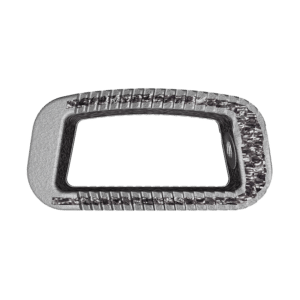

Rods:

- 4.75mm diameter Cobalt-Chrome-Molybdenum (CoCrMo) alloy

- 5.5mm diameter* Ti6Al4V and CoCrMo rods

- Straight and pre-lordosed configurations